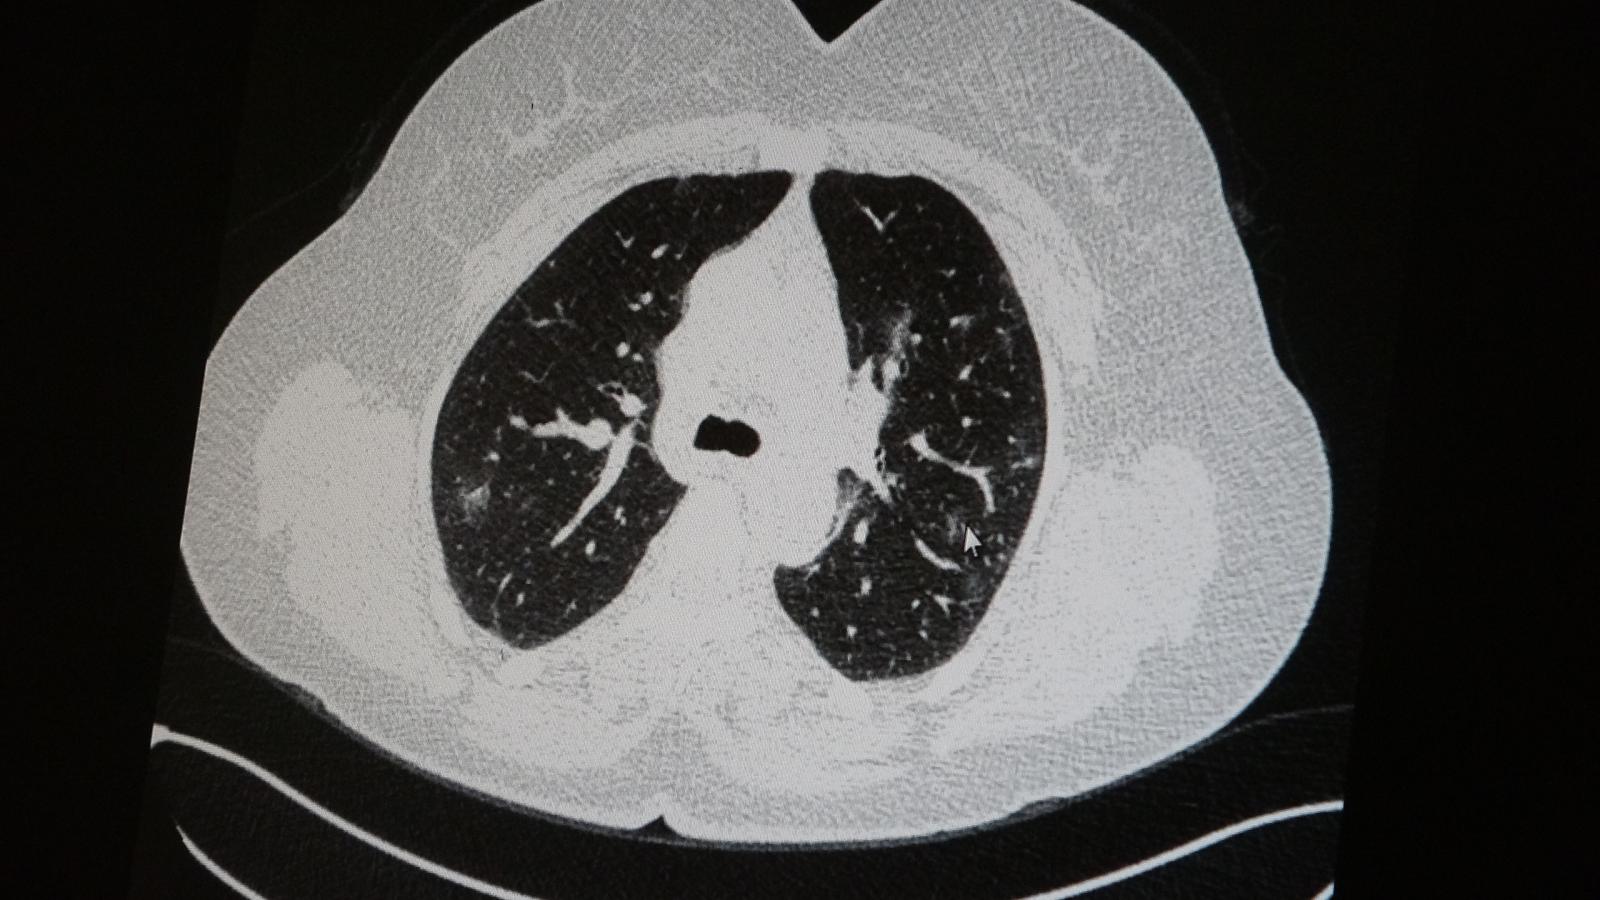

Elazığ’da öksürük, halsizlik, yorgunluk ve çabuk yorulma gibi şikayetlerle hastaneye başvuran ve koronavirüs tespit edilen 2 genç hastadan aşısız olanının tomografi sonuçlarında virüsün akciğerlerde zatürreye sebebiyet verdiği görüldü. Aynı şekilde aşı olup koronavirüs hastalığına yakalanan bir başka genç hastanın bilgisayarlı akciğer tomografisinde akciğerinde herhangi bir sorunun olmadığı belirlendi.

Medical Park Elazığ Hastanesi Göğüs Hastalıkları Uzmanı Dr. Cebrail Azar, geçtiğimiz yıla oranla yoğun bakımda yatan hastaların yaş ortalamasının 65’ten 35’lere kadar düştüğüne dikkat çekti. Genç olduğu halde aşı olmayanlarda hastalığın ağır seyrettiğini ifade eden Uzm. Dr. Azar, “Ben gencim, benim bağışıklık sistemim kuvvetli” diyen genç bir hastanın akciğerlerinde ciddi lekelenmelerin olduğunu ve koronavirüs zatürresi olduğunu gördüklerini belitti. Uzm. Dr. Azar, aynı şekilde aşı olup koronavirüs hastalığına yakalanan bir başka genç hastanın akciğer tomografisinde akciğerde herhangi bir sorunun olmadığını ve hastanın durumunun iyi olduğunu gözlemlediklerini kaydetti. Uzm. Dr. Azar, sürekli şahit oldukları “Keşke biz aşı olsaydık” sözünü bir daha duymamak için herkesi aşı olmaya davet etti.